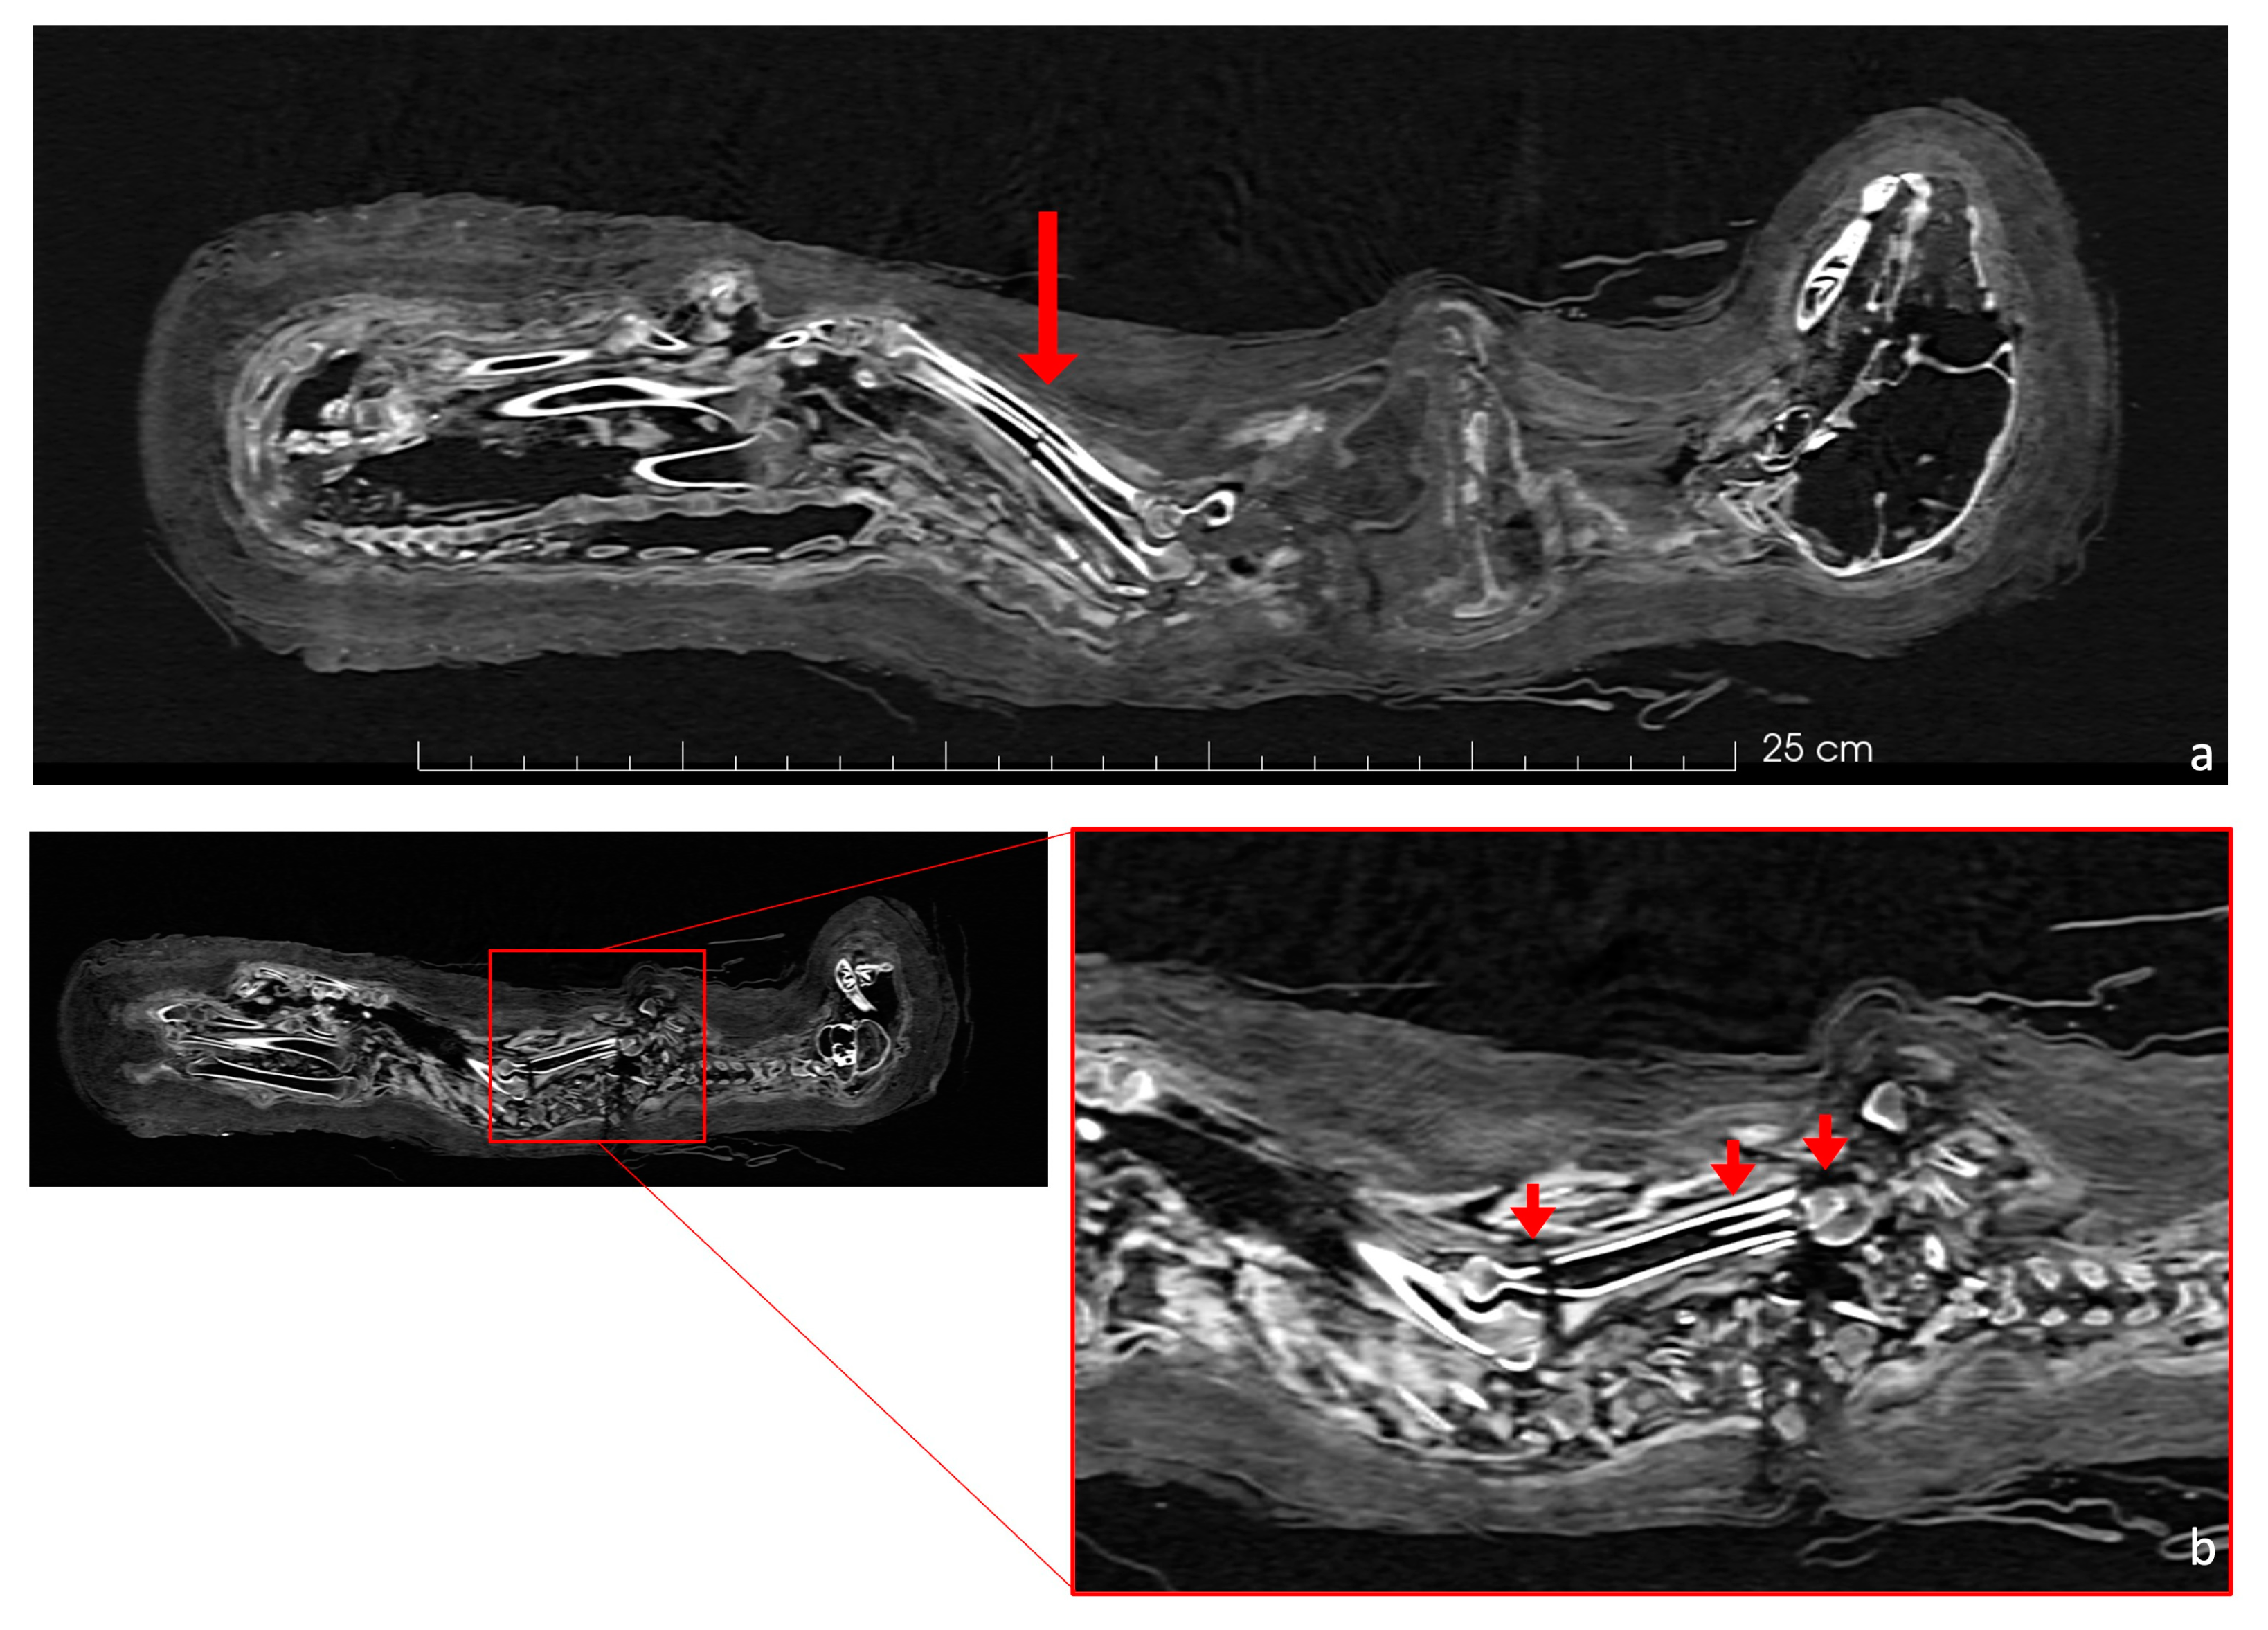

The central part of the body was severely damaged, with all the ribs and several vertebrae displaced from their normal positions. The last cervical vertebra (C7) and the thoracic vertebrae were completely fragmented, while the remaining cervical, lumbar, and caudal vertebrae had experienced less damage and remained in their correct positions (Figure 7a). The first ribs were visible and showed minimal fracturing, even though they appeared rotated by 180 degrees (Figure 7b), contrarily to the other ribs, which were extensively damaged.

Figure 7.

In the coronal view (a), the skeleton shows the cervical and lumbar vertebrae correctly positioned (highlighted by yellow arrows). However, the thoracic vertebrae are severely dislocated and fragmented. In the axial CT scan (b), attention is drawn to two first ribs that are rotated 180 degrees from their normal position (highlighted by red arrows).